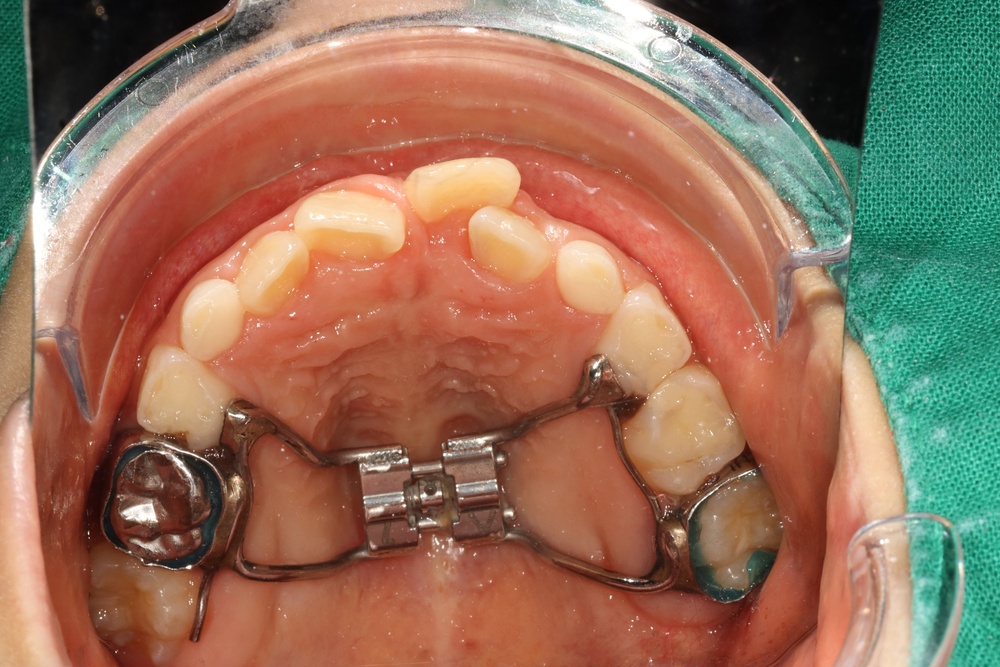

앞니가 비뚤게 나서 교정하러 온 친구입니다.

입천장의 고정식 확장장치를 이용해 좌우로 벌려서 치아를 배열할 공간을 만들었습니다.